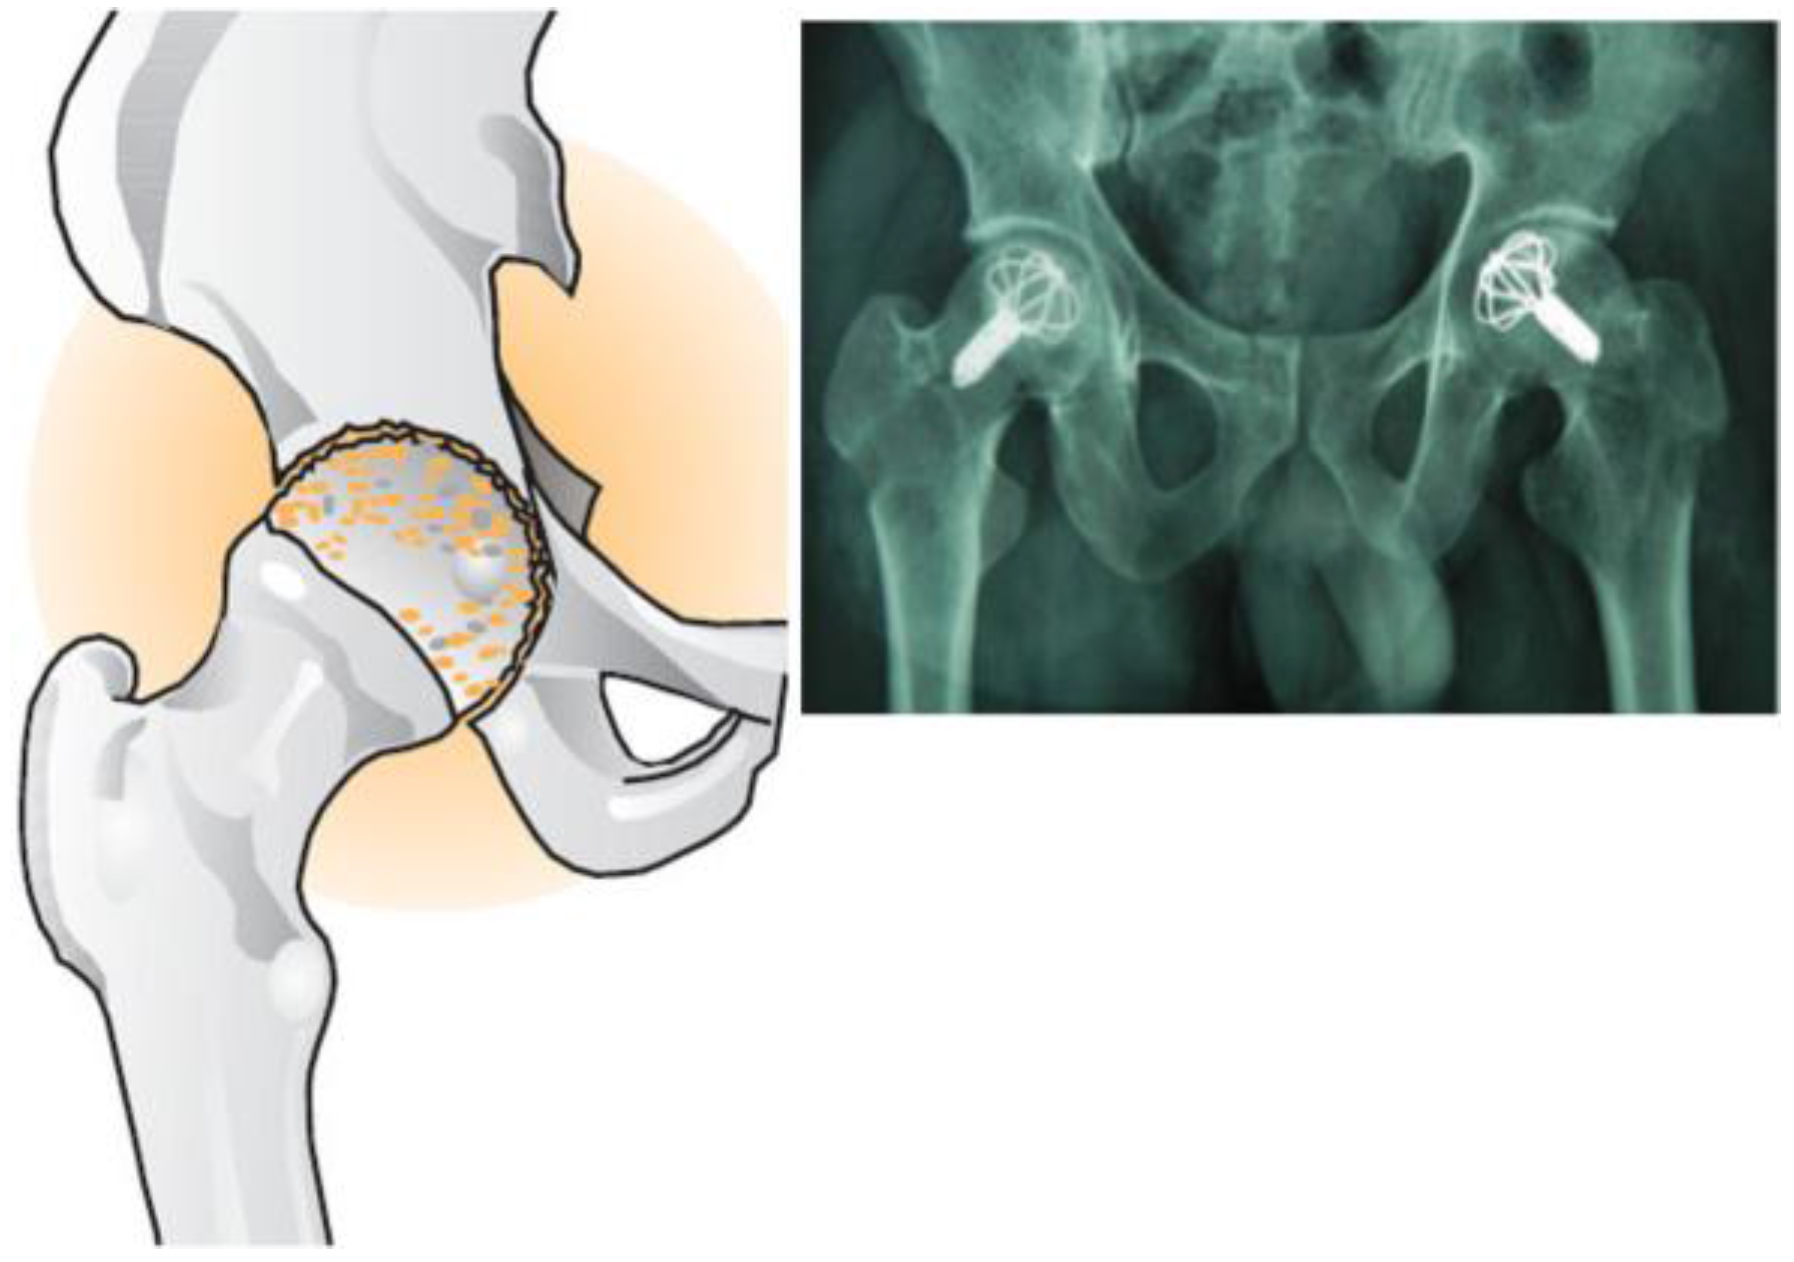

Finite Element Simulation of NiTi Umbrella-Shaped Implant Used on Femoral Head under Different Loadings

- Yu, X.; Jiang, W.; Pan, Q.; Wu, T.; Zhang, Y.; Zhou, Z.; Du, D. Umbrella-shaped, memory alloy femoral head support device for treatment of avascular osteonecrosis of the femoral head. Int. Orthop. 2013, 37, 1225–1232. [Google Scholar] [CrossRef] [PubMed]